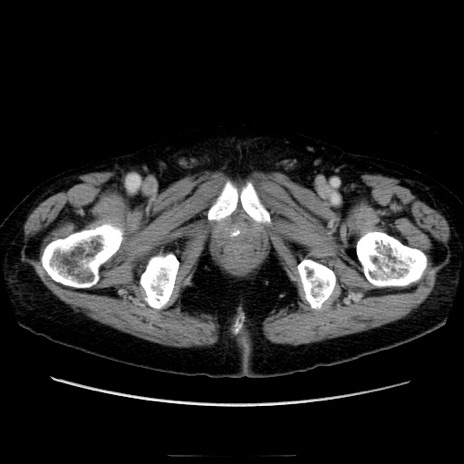

症例21(横断像)

【症例】70歳代男性

【主訴】腹痛

【現病歴】肝硬変・肝細胞癌にてかかりつけの方。約9時間前に食後より腹痛出現。症状が徐々に増悪し、嘔吐出現したため来院。

【既往歴】肝硬変、肝細胞癌(RFA、TACE後)

【身体所見】意識清明、表情苦悶様、BT 36℃、BP 129/78mmHg、P 88bpm、SpO2 97%(RA)、右上腹部から心窩部にかけて圧痛あり、反跳痛なし、筋性防御あり。

【データ】WBC 5800、CRP 0.16